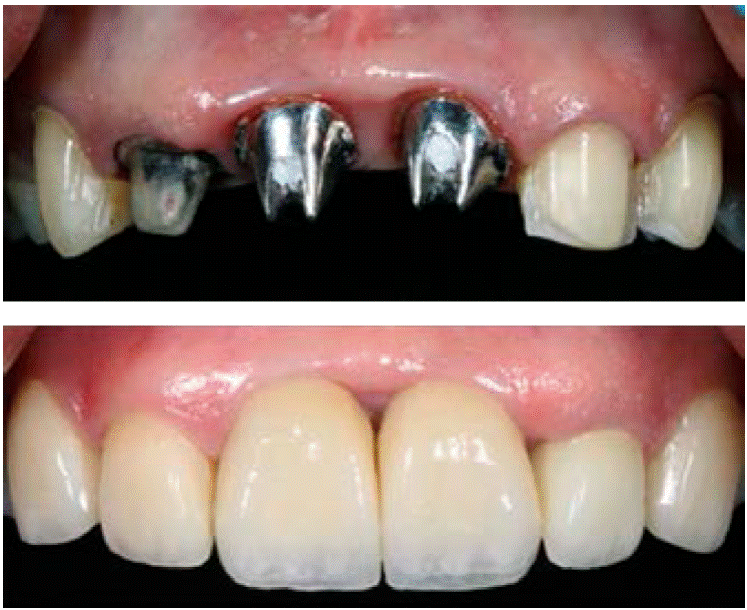

Carillas en los dientes 1.3, 1.2 y 2.3; coronas en 1.1, 2.1 y 2.2, además de pilares metálicos de las piezas 1.1 y 2.1 listas para cementar (Figuras 15y16).

Cabe mencionar que en las coronas sobre implantes se conformó el punto de contacto bajo para poder lograr la altura ideal entre la cresta y éste que es de 5 mm y conservar la anchura biológica del perfil de emergencia y en especial la papila.

Dejando así una comparativa de cómo llegó el paciente y cómo fue la conclusión del caso (Figura 18y19).